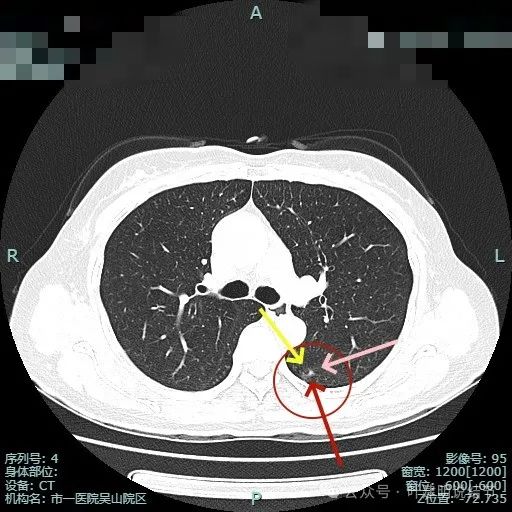

右上主病灶出现(病灶2),离肺门部非常近,密度较淡。

病灶1有明显叶间裂牵拉影响;病灶2密度虽淡,但轮廓清,贴着支气管壁。也有小血管走向病灶。

病灶1密度已经淡了;病灶2刚好位于上叶支气管发现后段支气管处,与支气管壁没显著间隙。